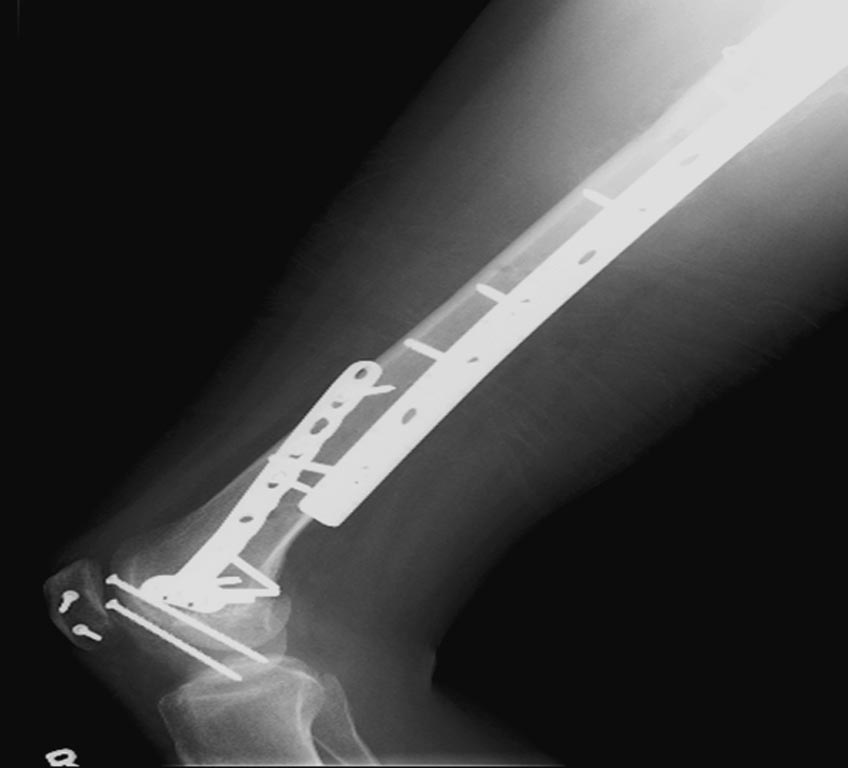

На 25 день с момента травмы операция на Jackson table с боковым обширным

доступом. Удаление стержней с местной обработкой. В тазобедренном

суставе удаление головки, на дне вертлужной впадины полная отслойка

хряща. Вертлужный компонент с одним винтом и короткая ножка -  Fitmore

Выписана. Нагрузку разрешили на левой стороне, а полная в 3 мес.  Здесь

снимки при амбулаторном наблюдении​: послеоперационно, 2 мес, 3 мес и 6

мес. Нагрузка полная, отсутствует хромота, и нет жалоб.